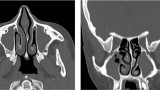

Diagnostyka obrazowa zatok staje się coraz bardziej istotna dla lekarzy dentystów, którzy posiadają w swoich gabinetach aparaty tomografii stożkowej (CBCT). W zależności od wielkości pola obrazowania w CBCT są widoczne fragmenty zatok szczękowych aż po całe zatoki szczękowe, a w badaniach o największym polu obrazowania wszystkie zatoki oboczne nosa, podobnie jak w badaniu medycznej tomografii komputerowej (TK). Z tego względu celem pracy jest przedstawienie najważniejszych zmian patologicznych zatok szczękowych, z którymi może się spotkać lekarz stomatolog, opisując badania tomografii stożkowej (CBCT).